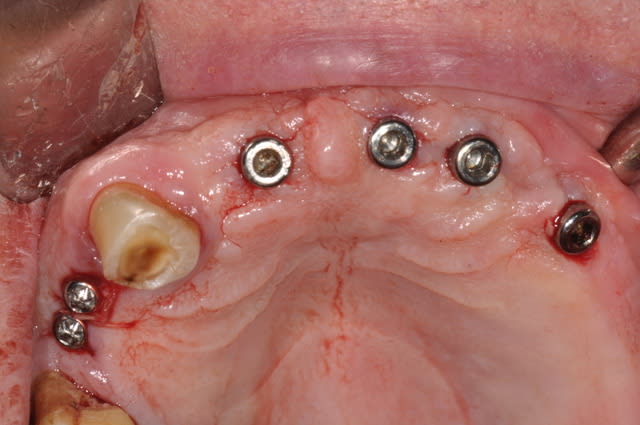

Patient 75ans traitement médical adhoc pour son age.

Implants posés le 31/05

juste une incision crestale au moment de la mise en place des implants, je n'arrive pas à faire tout transgingival comme le fait notre confrère Nedjat avec ses implants.

le cas de ce matin

Patient 80ans ne veut plus de PAP

Première tentative en transgingival

Je te mets la cicatrisation à 24h,çà me plait bien, ce sont des implants Léone